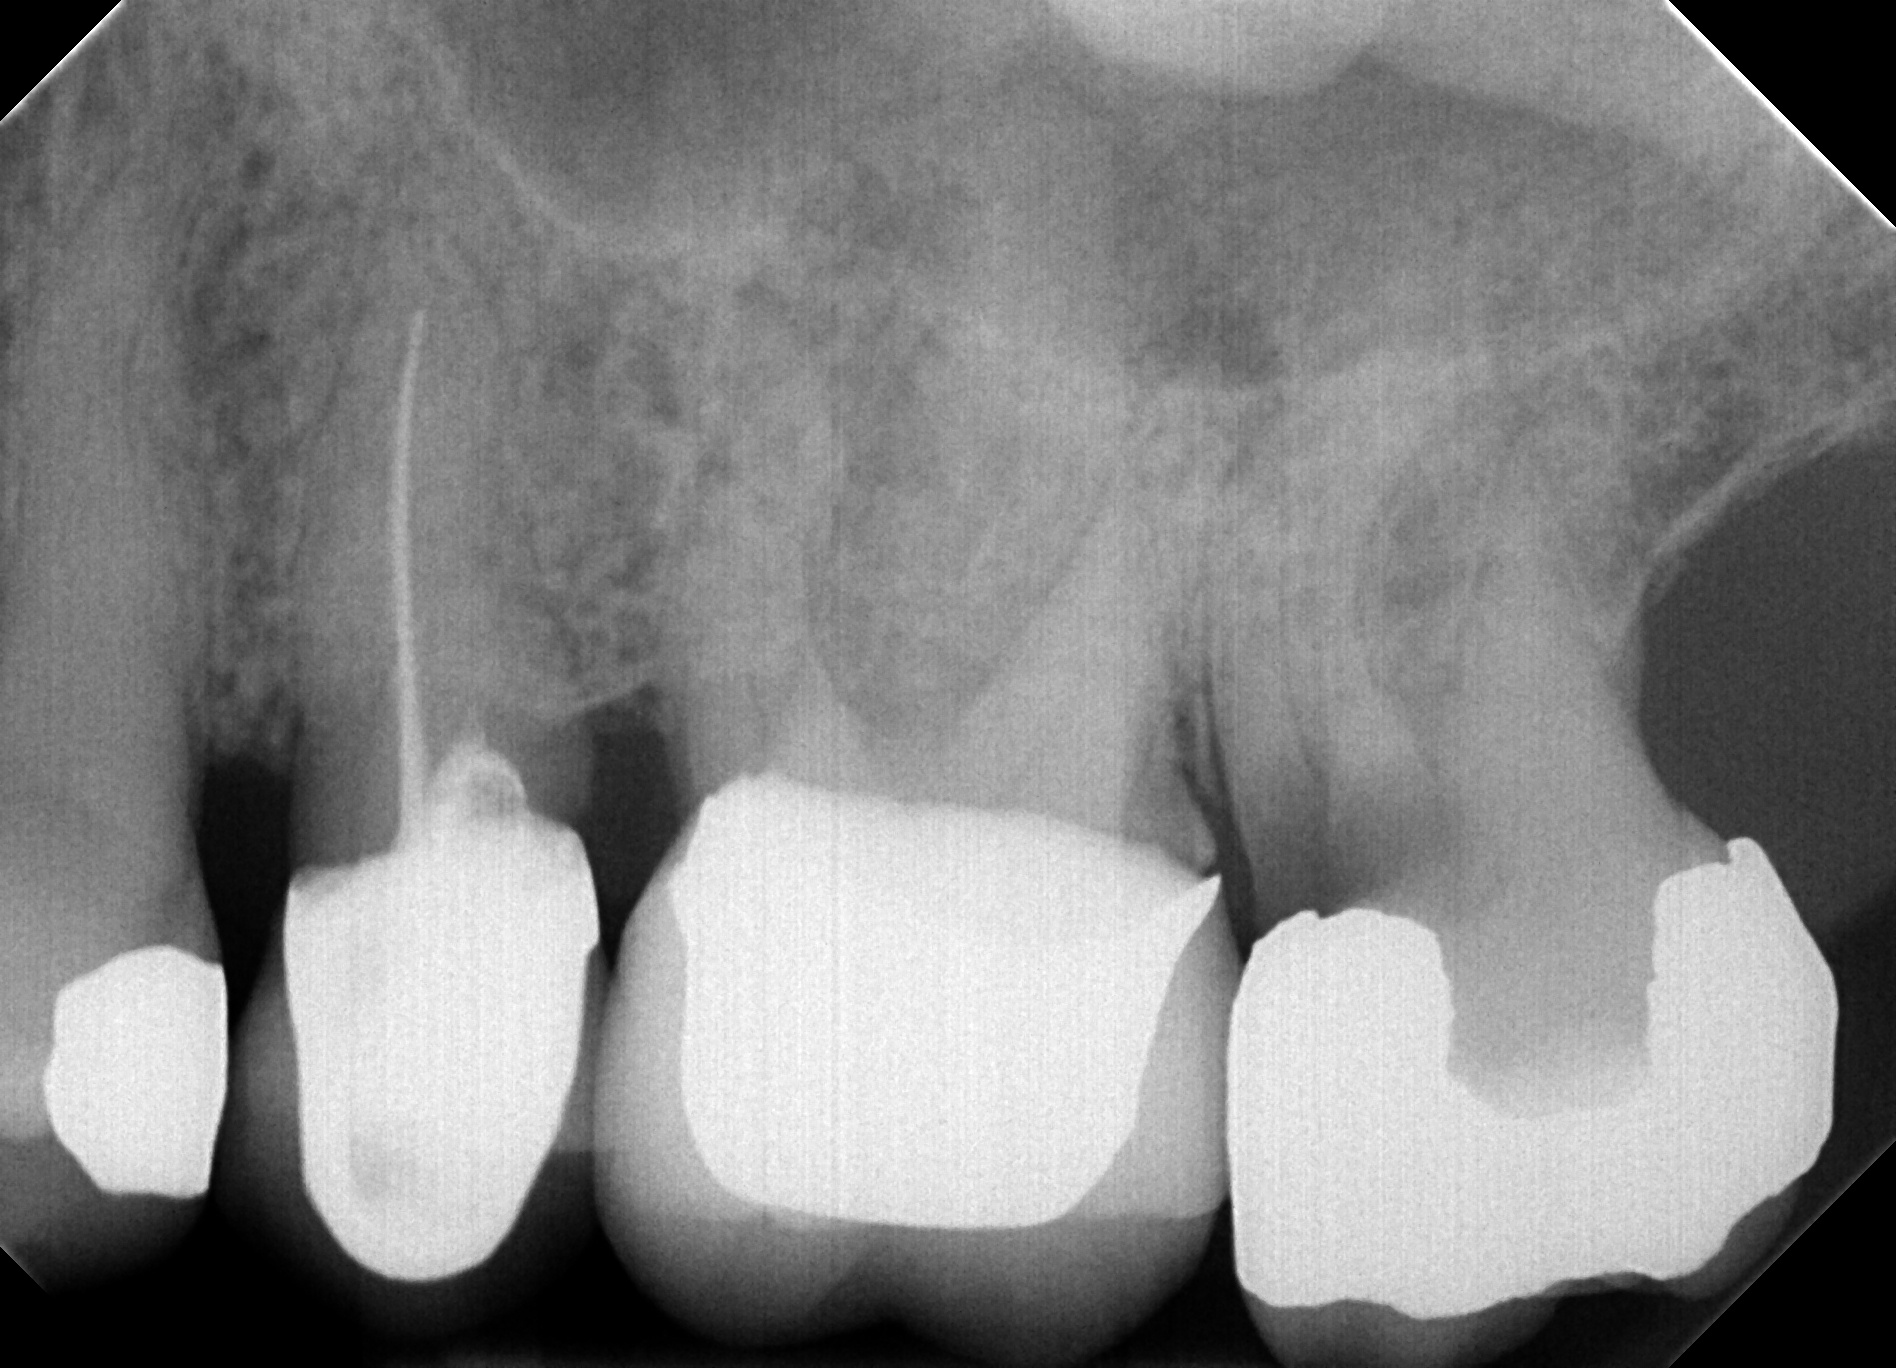

In the first part of the clinical study, called the control arm, a benchmark was set for the regular workflow of inspecting intraoral images. First of, the IOR images were randomly divided into disjunct subsets of (or in one case ) images. Seven new dentists (with either DDS or DMD qualifications and sufficient clinical practice) were asked to each analyze one of these subsets of unprocessed IOR images for the six anomaly categories listed in § 1. To facilitate and track the evaluation, these dentists manually annotated the original IOR images by drawing rectangular bounding boxes at the location of the various anomaly instances that they could distinguish. The annotations were made using the online image annotation tool Supervisely (https://supervise.ly). The bounding boxes for each anomaly type all have a predefined color. An example is shown in Fig. 1.

In the study portion of the clinical validation study, each of the seven dentists was shown the same series of (or ) images as in the control arm. In this case, the images were already analyzed beforehand by the AI-based anomaly detection algorithm. The anomaly locations predicted by the algorithm were also depicted on the IOR image using the setup with colored bounding boxes in the annotation tool. The dentists were asked to look for the six anomaly types in each IOR image in their respective image batch using the algorithmic output for guidance. In practice, the dentists could leave the annotating bounding boxes in place for the anomalies that they were in agreement with. Note that repositioning and resizing the boxes was also possible. Further, they were asked to remove all boxes for anomalies that they judged not to be there. Additionally, they could add boxes for anomalies that they considered to be undetected by the AI algorithm. The end results were stored as the algorithm-assisted annotated images. To avoid any recall bias, an idle period of 4 weeks was implemented in between the control and study phase. Also, we switched the order of the control and study phase for three randomly chosen dentists.